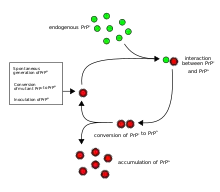

Prions cause neurodegenerative disease by aggregating extracellularly within the central nervous system to form plaques known as amyloids, which disrupt the normal tissue structure. This disruption is characterized by "holes" in the tissue with resultant spongy architecture due to the vacuole formation in the neurons.[66] Other histological changes include astrogliosis and the absence of an inflammatory reaction.[67] While the incubation period for prion diseases is relatively long (5 to 20 years), once symptoms appear the disease progresses rapidly, leading to brain damage and death.[68] Neurodegenerative symptoms can include convulsions, dementia, ataxia (balance and coordination dysfunction), and behavioural or personality changes.

It has been recognized that prion diseases can arise in three different ways: acquired, familial, or sporadic.[77] It is often assumed that the diseased form directly interacts with the normal form to make it rearrange its structure. One idea, the "Protein X" hypothesis, is that an as-yet unidentified cellular protein (Protein X) enables the conversion of PrPC to PrPSc by bringing a molecule of each of the two together into a complex.[78]